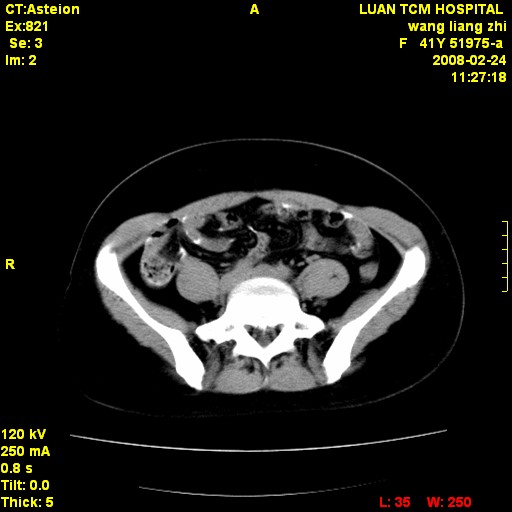

以下是引用dyqct在2009-8-23 16:17:00的发言:[br]考虑:1、造影剂进入腹腔、结肠旁沟、肝周;[br] 2、子宫明显增大(腺肌增生症?);[br] 3、膀胱显影是由于造影剂吸收后经肾分泌进入膀胱的;[br] 4、建议mri检查子宫。